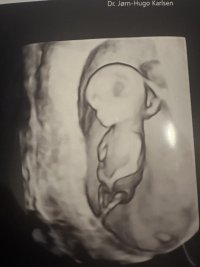

Ikke ett ideelt bilde, har du flere? Men ser ut som man kan se at det begynner å utvikles testikler, så jeg ville også sakt gutt. Her er min yngste gutt.Jeg var på TOUL på torsdag, 14+0. Alt bra og en aktiv liten baby